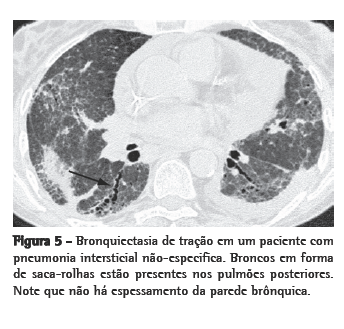

Bronquiectasia de tração

A dilatação dos brônquios como conseqüência da fibrose intersticial é referida como bronquiectasia de tração (Figura 5). Os brônquios têm geralmente aparência irregular (saca-rolhas) e não estão associados com evidências radiológicas de inflamação brônquica (espessamento grosseiro da parede brônquica ou impactação mucóide). A bronquiectasia de tração é geralmente acompanhada por outros sinais de fibrose pulmonar (faveolamento ou reticulação irregular). Apesar da bronquiectasia de tração ser bastante específica para a fibrose, o diagnóstico diferencial é mais amplo do que aquele para faveolamento. A fibrose pulmonar idiopática (FPI) é comumente associada à bronquiectasia de tração. Entretanto, na ausência de faveolamento, outras doenças são mais prováveis (Quadro 3). Em pacientes com histórico de doença do colágeno vascular, a bronquiectasia de tração bibasal e periférica, acompanhada de atenuação em vidro fosco, pode ser considerada como diagnóstico de PINE. Quando as circunstâncias são menos diagnósticas, pode ser necessária uma biópsia cirúrgica.